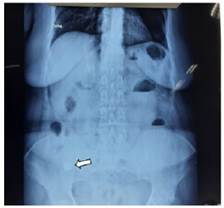

Paciente femenino de 68 años de edad, dentro sus antecedentes patológicos quirúrgicos, refiere apendicectomía convencional hace 40 años y clínicos una diabetes mellitus en tratamiento; cuadro clínico de 1 semana de evolución caracterizado por presentar, dolor abdominal tipo cólico generalizado, nauseas que llegan al vomito en varias oportunidades tipo bilioso, distensión abdominal; por lo que acude a una clínica particular donde es internado por 4 días y manejado con medicamentos que no refiere; en forma posterior solicita el alta hospitalaria, por lo que acude a nuestra institución. Al momento de su evaluación presentaba vómitos fecaloideos en varias oportunidades; signos vitales estables. Al examen físico segmentario; cardiopulmonar clínicamente estable; abdomen con leve distensión a expensas de gases, ruidos hidroaéreos positivos pero hipoactivos, dolor a la palpación profunda en epigastrio e hipogastrio, resto de examen sin particular. Se realizaron los exámenes complementarios correspondientes: Laboratorios. GB:18 160 109/L, segmentados 88 %, TP 12 segundos, INR 1,17, hemoglobina 13.2 gr/ dl, Plaquetas 463 000 109/L. Rayos X de abdomen (Figura 1), se puede observar imagen radiolucida en fosa iliaca derecha.

Figura 1 Rayos X de abdomen donde se evidencia imagen radiolucida (lito) en fosa iliaca derecha (flecha blanca indica el lito).

Para el diagnóstico se solicitan estudios de imagen, como una radiografía de abdomen y en los hallazgos se busca la famosa tríada de Rigler, que consiste en la presencia de cálculos radiopacos (presentándose en menos del 10 % de los casos), neumobilia (signo de Gotta-Mentschler), y distensión de las asas intestinales; la presencia de 2 de los 3 signos establece el diagnóstico11; en nuestro caso se puede evidenciar claramente 2 criterios que son, presencia de lito y datos de distención intestinal. El estudio de preferencia es la tomografía de abdomen, la cual puede confirmar el diagnóstico, permitir localizar el sitio de obstrucción, determinar presencia de neumobilia, y planificar el tratamiento12; en el caso de nuestro paciente este examen claramente reflejo el diagnostico en mención.